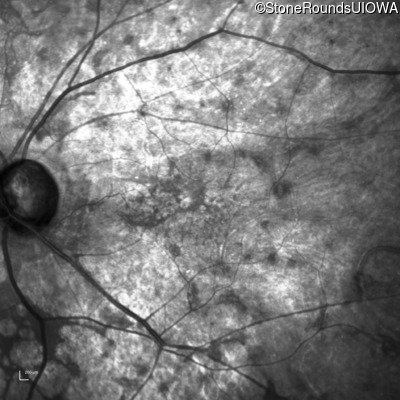

This 81 year old man began using a flashlight to read menus in his 40's. At age 75 his ophthalmologist noticed abnormal fundus findings and referred him to a retina specialist.

| Age at visit: 81 years |

| Age at visit: 82 years |

| Age at visit: 83 years |

| Age at visit: 84 years |

| Age at visit: 85+ (Visit 1) |

| Age at visit: 85+ (Visit 2) |